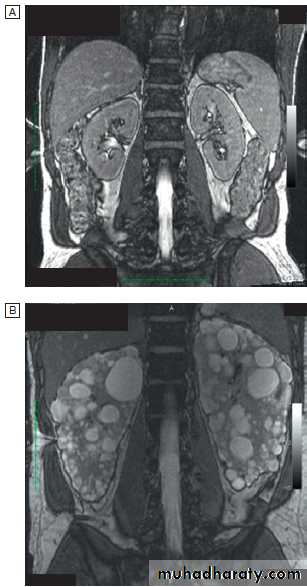

Magnetic resonance imaging (MRI)

offers excellent resolution . It is very useful for local staging of prostate, bladder and penile cancers. MR angiography alternative to CT-angiography for imaging renal vessels.Renal arteriography